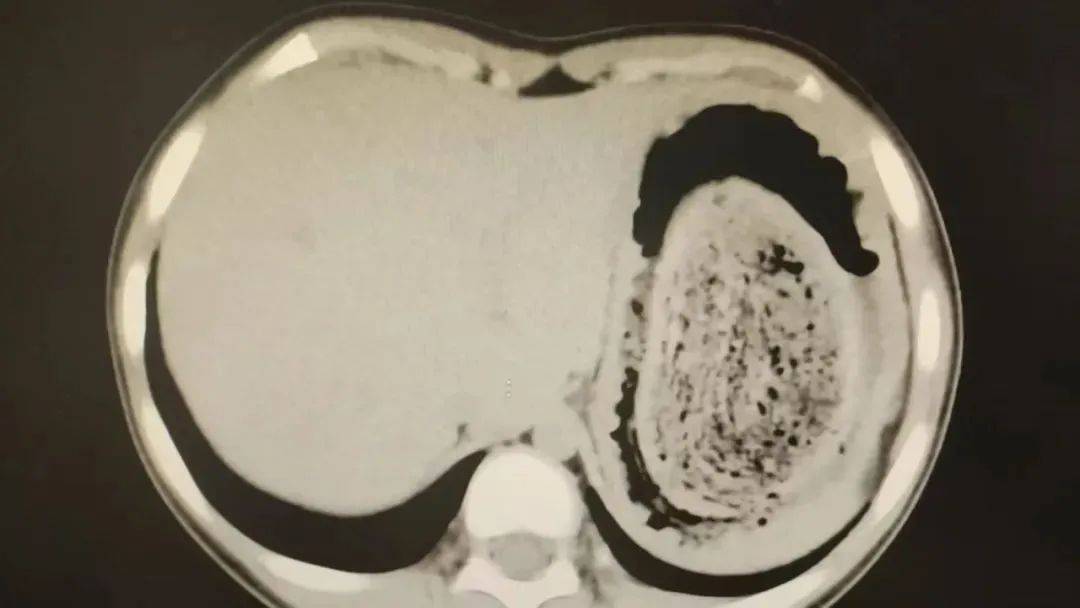

在胃镜帮助下,妮妮胃里的情况逐渐明了皇冠登3管理出租 。一个滚圆黑色的毛发球混合着食物残渣占据整个胃腔,这些头发相互缠绕形成一个实心的“发石”,此外胃里还有一个鸡蛋大小的溃疡。

症结找到了,就是这个巨大的发石导致妮妮出现营养不良、贫血和闭经,当务之急就是取出“发石”,给胃进行“大扫除”皇冠登3管理出租 。

头发缠绕在一起十分坚硬,体积巨大,胃镜尝试多次均难以取出,医护人员不得不采取开放手术的方式来取“发石”皇冠登3管理出租 。

“发石”混杂着食物残渣,就像一个黑色的小西瓜皇冠登3管理出租 。由于整个“发石”体积太大,为避免损伤胃壁,医生借助手术工具将“发石”切割、分解,再小心翼翼地分块取出。整场手术持续2个多小时,最终取出4斤头发碎片。

10岁女孩园园(化名)因持续3天的上腹痛伴呕吐被紧急送医皇冠登3管理出租 。影像学检查结果显示,她的胃部存在一个巨大的团块状阴影,初步怀疑为异物堵塞。据家长回忆,园园从1年前开始就有偷偷吃头发的习惯,但家人并未重视,直到这次症状严重才意识到问题的严重性。